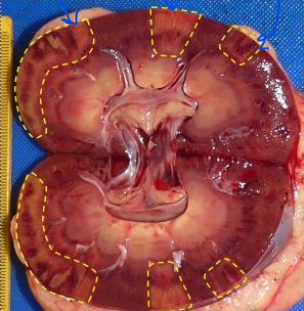

What does this image show?

cut surface of the normal kidney

What type of pathological change is most likely to have affected the renal parenchyma?

atrophy

What has caused the parenchymal atrophy?

pressure build up repressing blood supply to tissue